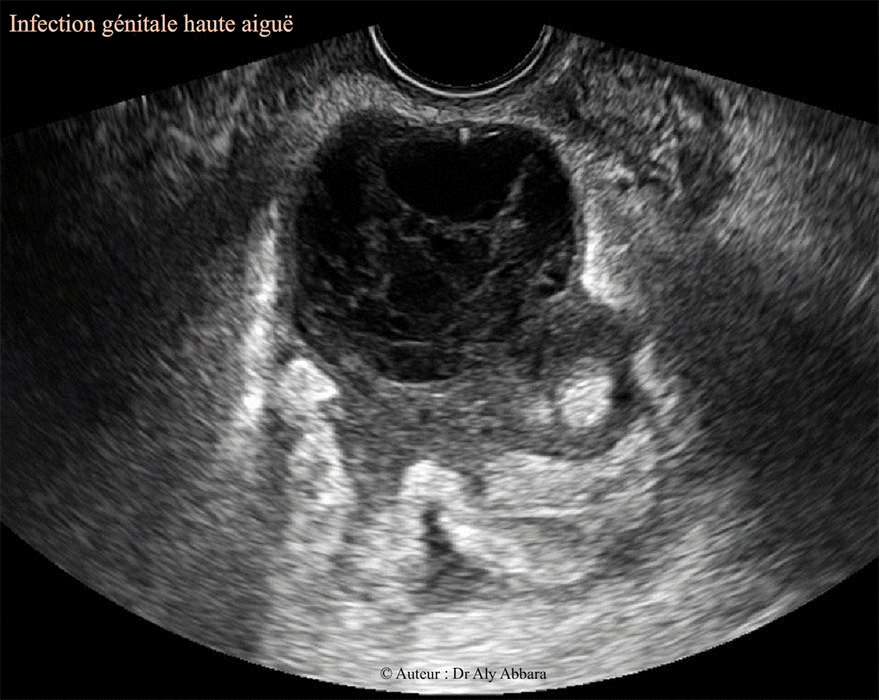

Salpingite aiguë et péritonite pelvienne - Echographie

Image animée montrant l'aspect échographique d'une

infection génitale haute, sévère : salpingite aiguë sans pyosalpinx ; abcès de l'ovaire et abcès péri-tubaire